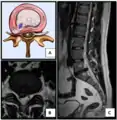

- Click images to see larger versions

Lumbar disc lesions, classification

Normal situation and spinal disc herniation in cervical vertebrae

Illustration depicting herniated disc and spinal nerve compression

Nucleus herniating through tear in annulus (with MRI)[9]

Illustration showing disc degeneration, prolapse, extrusion and sequestration